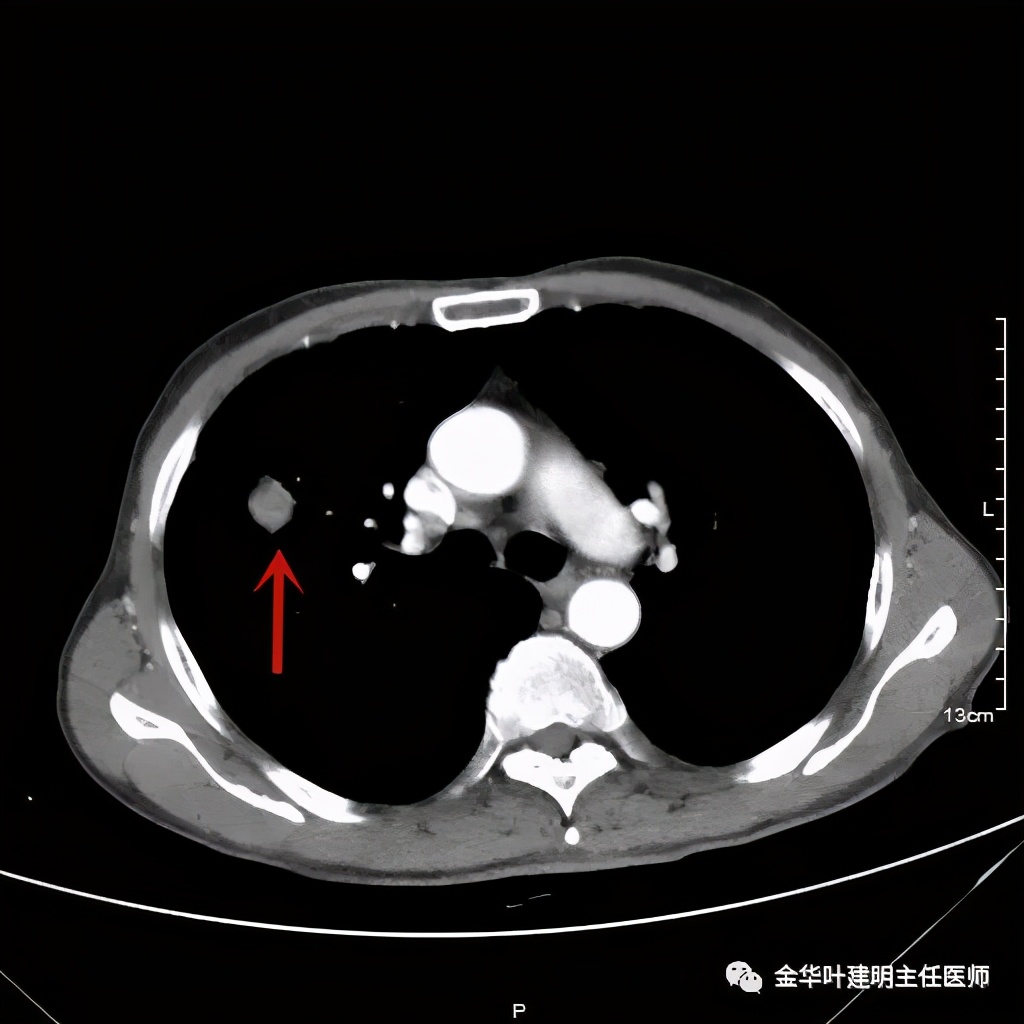

上图示纵隔窗实性

上图箭头示强化的血管与病灶关系密切,而且有被病灶侵犯影响的感觉,部分界限是不清楚的